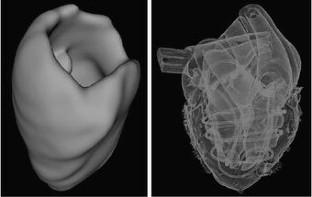

Fig 5.

Fig 6.